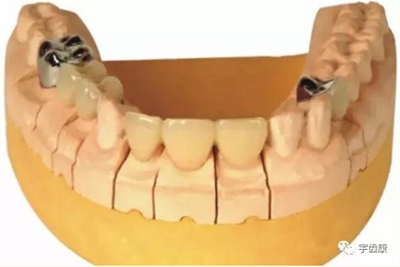

7. 共同就位道的調(diào)節(jié)

8. 實(shí)際備牙產(chǎn)生的問題